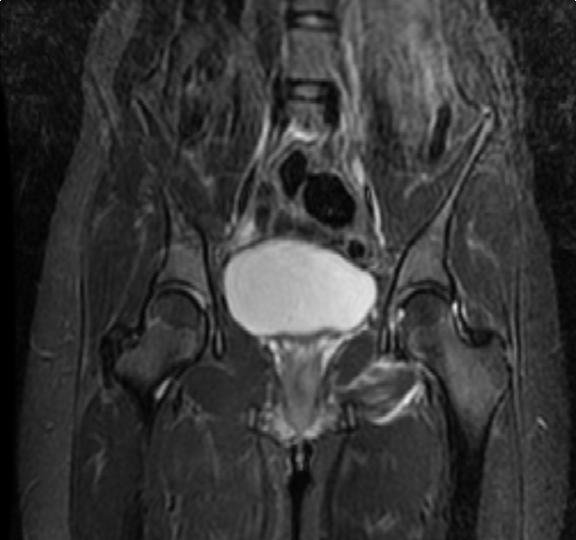

Radiographs of the pelvis showed posterior dislocation of the hip without fracture of acetabulum or femoral head. (Figure 1) (Figure 2) Type 1 dislocation was diagnosed according to Thompson and Epstein classification. The dislocation was reduced immediately under conscious sedation (midazolam 5 mg intravenous) after diagnosis. Allis’s maneuver was used for reduction. There was no sciatic nerve deficit before and after reduction. Skeletal traction was not applied. X-ray and magnetic resonance imaging (MRI) scan revealed concentric reduction of the hip joint. (Figure 3) Indomethacin 75 mg was begun for heterotopic ossification prophylaxis. Early mobilization allowed without weight bearing. Hip flexion over 90 degrees and internally rotation over 10 degrees were prohibited. She was followed-up for six weeks with gentle abductor and quadriceps strengthening exercises and weight bearing was allowed then. The patient was well six months after dislocation with normal activities.

Figure 3: Postreduction magnetic resonance imaging scan showing piriformis edema in left hip.